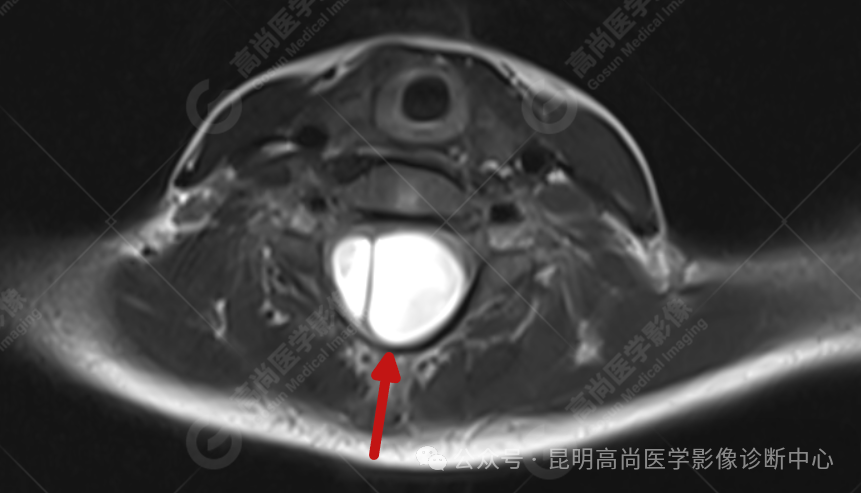

患者女,5 岁,出生时发现颈部包块,大小 3 cm×3 cm,5 年来无变化,拟行手术治疗,要求增强核磁协诊,否认体内金属物,无过敏史。

颈 3-5 层面颈后部软组织不规则片状异常信号影,脊膜膨出可能;颈 3、4 棘突局部显示不清;颈胸髓内(约颈 3-胸 9 椎体水平)异常信号影,考虑囊肿并局部颈髓空洞可能,肿瘤或其他待排;请结合临床及相关检查。

(2)脊膜膨出:神经管闭合,脊髓正常,周围组织闭合不全,脊膜从不连接处膨出,形成囊肿样改变,其内包含脑脊液。

(2)磁共振 (MRI) 检查:是目前对神经系统最直观的检查,可发现脊髓、脊神经及脊膜的膨出情况。可发现脊神经本身病变如脊髓空洞;椎管内有否肿物 (囊肿)、脂肪,以及粘连、脊髓低位或终丝粘连等;可见脊膜膨出内有否脊神经、神经纤维等;横断面还可见脊柱裂大小及范围。明确脊膜膨出的类型,有否合并脊髓拴系。